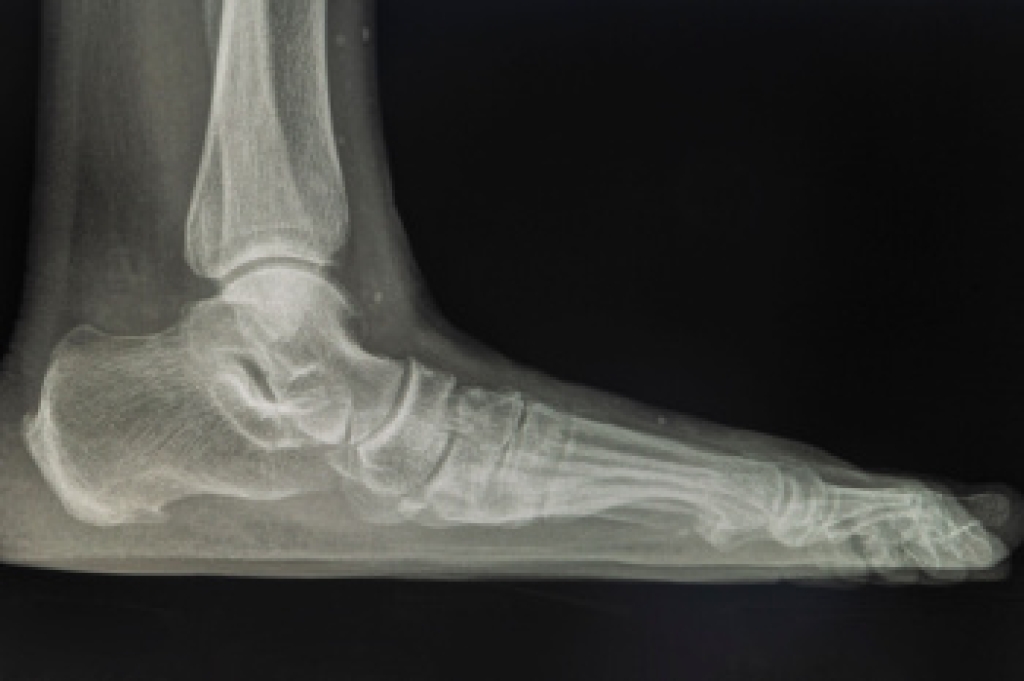

The most common injuries that occur in sporting activities include:

- Achilles Tendonitis

- Achilles Tendon Rupture

- Ankle Sprains

- Broken Foot

- Plantar Fasciitis

- Stress Fractures

- Turf Toe